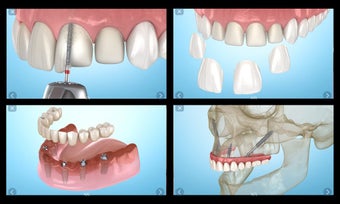

إذا كنت متخصصًا في طب الأسنان أو مريضًا، فقد تساعدك هذه الأداة في تعلم علاجات الأسنان.

تم إنشاء هذا التطبيق بواسطة أليكس ميت للأطباء الأسنان وطلاب طب الأسنان والمرضى. كما يمكن استخدامه أيضًا من قبل المهنيين الطبيين الآخرين.

يستند التطبيق على مبدأ عرض الشرائح. يحتوي كل موضوع على 3-9 صور. يمكن عرض صور أي موضوع في أي وقت.